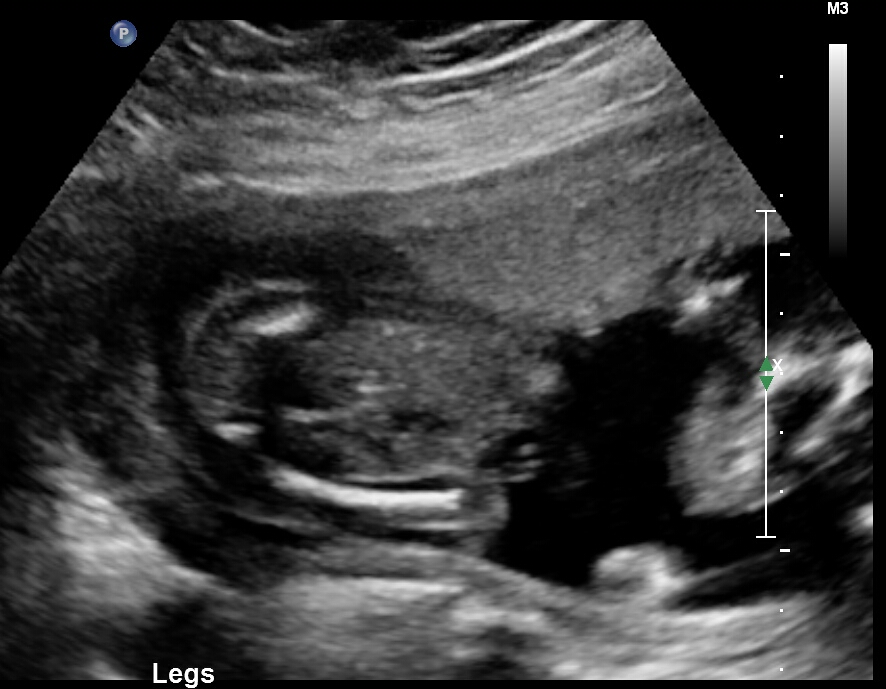

Just wondering if any gender clues can be seen in these pics? Attachment 37755Attachment 37756Attachment 37757